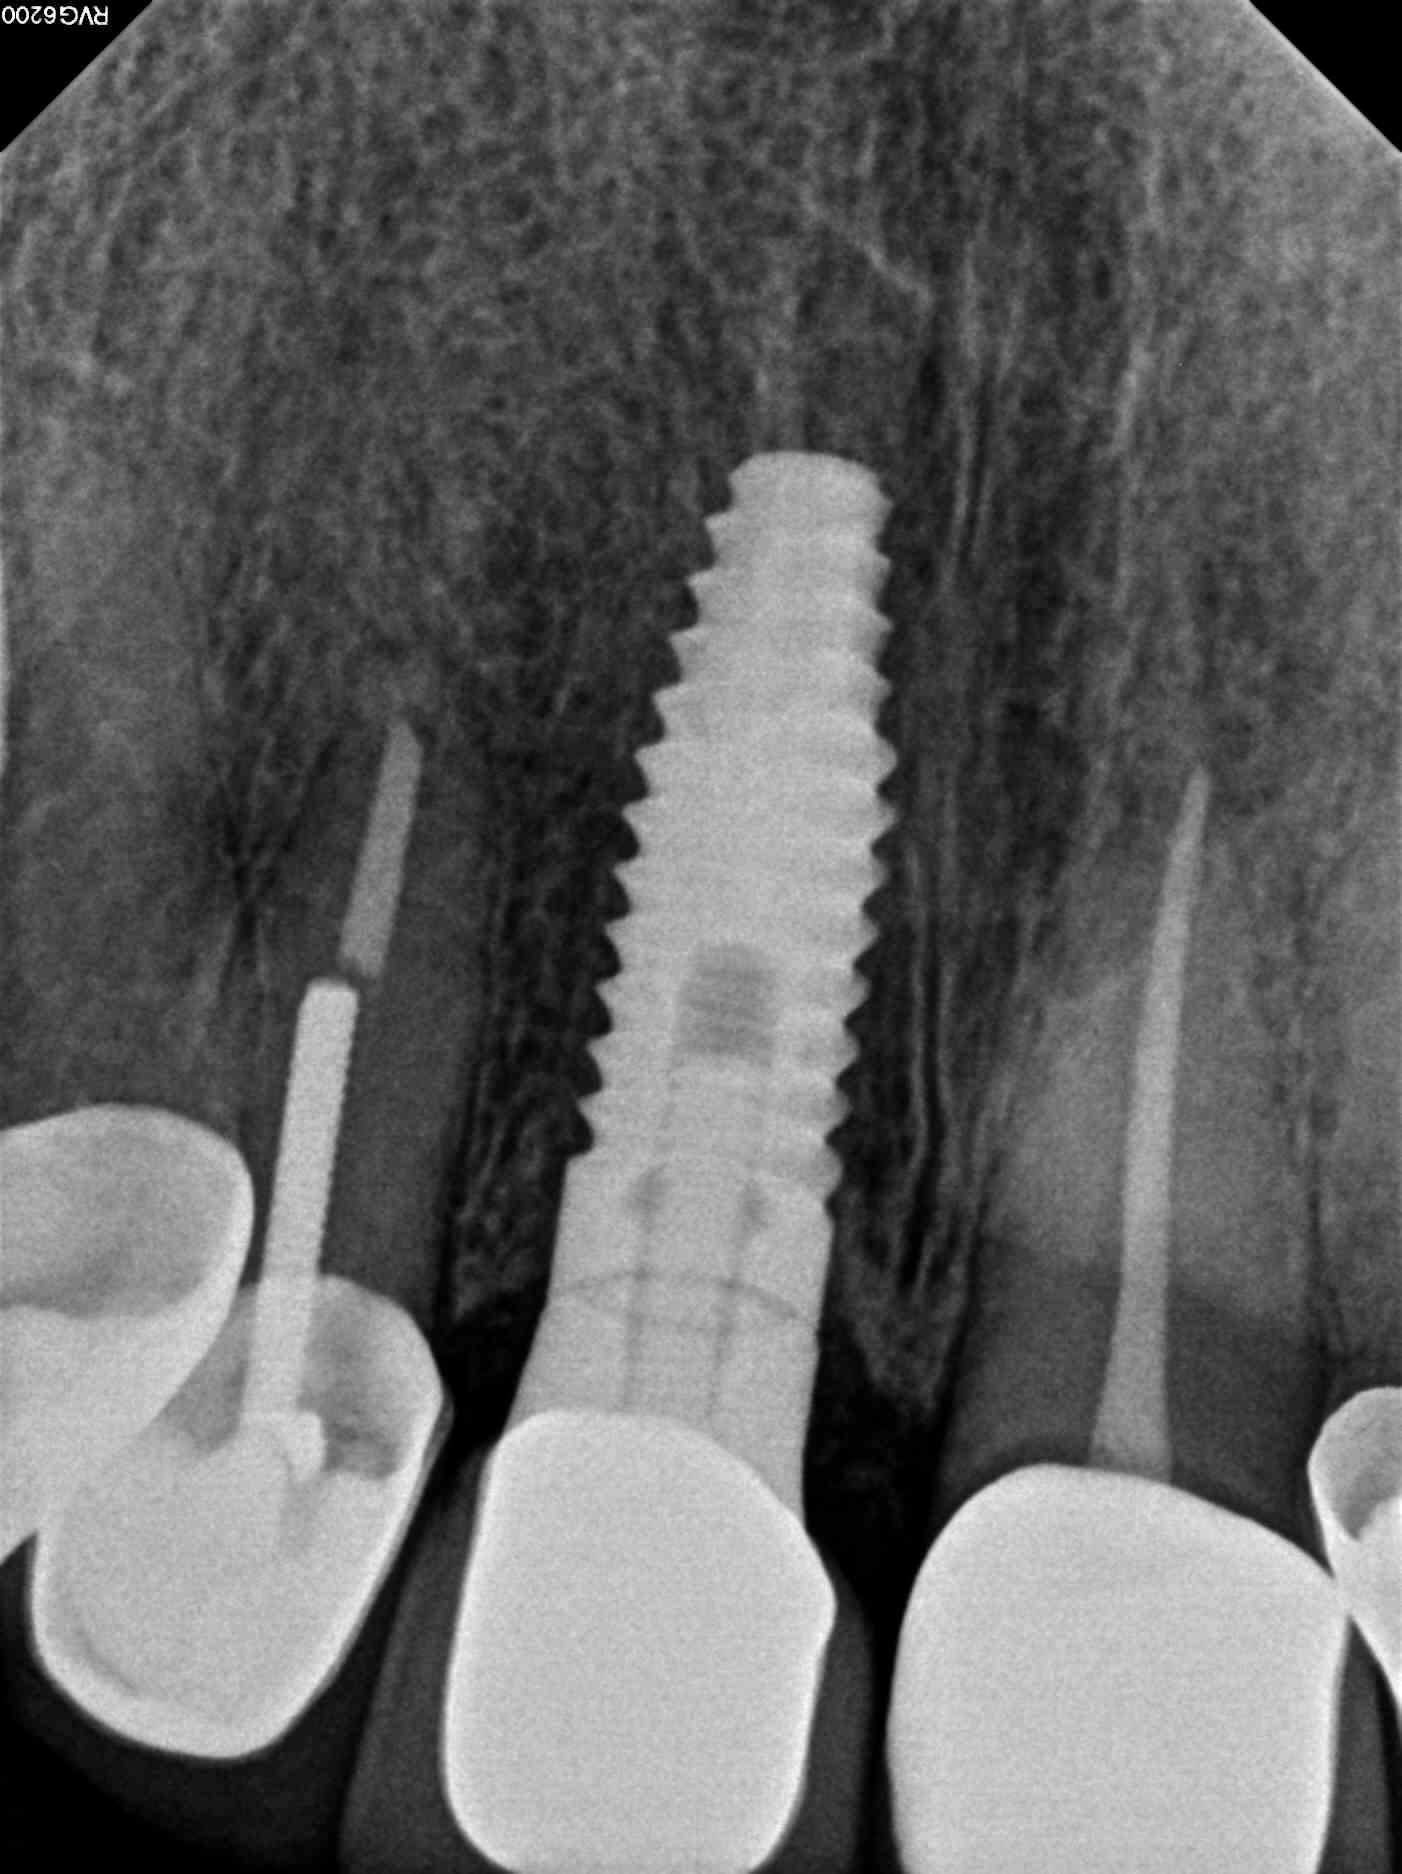

Front tooth restored with dental implant

Our patient had fractured a front tooth in an accident and needed a quick and permanent fix for her front tooth. The tooth was extracted and an immediate implant was placed the same day. After 4 months of healing we achieved an excellent emergence profile and a custom titanium abutment was torqued in. A permanent porcelain fused to metal dental crown was placed in the #8 area (to match her other crowns). We attached photos for this case. During treatment planning a CBCT scan was done of the upper arch to diagnose the qaulity and the quantity of the bone in this area. Dr. Yamen Akhras places dental implants at his office, where general dentistry and orthodontics are also services that are offered. Call today for a consultation with the doctor.